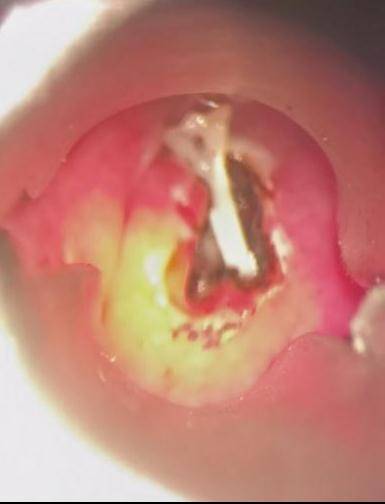

经过详细检查 , 哈医大四院耳鼻咽喉头颈外科主任周彬为王先生进行急诊全麻下支撑喉镜下下咽后壁切开异物取出术 。 术中可见咽后壁粘膜光滑 , 会厌高度偏左侧的咽后壁略隆起 。 在隆起处以激光纵行切开粘膜及粘膜下组织 , 脓性液体流出 , 其内可见一白色鱼刺 。 完整取出鱼刺 , 可见其上端呈针尖状 , 整体呈弧形 , 边缘锐利光滑 , 无破损 。 术后 , 王先生恢复良好 。